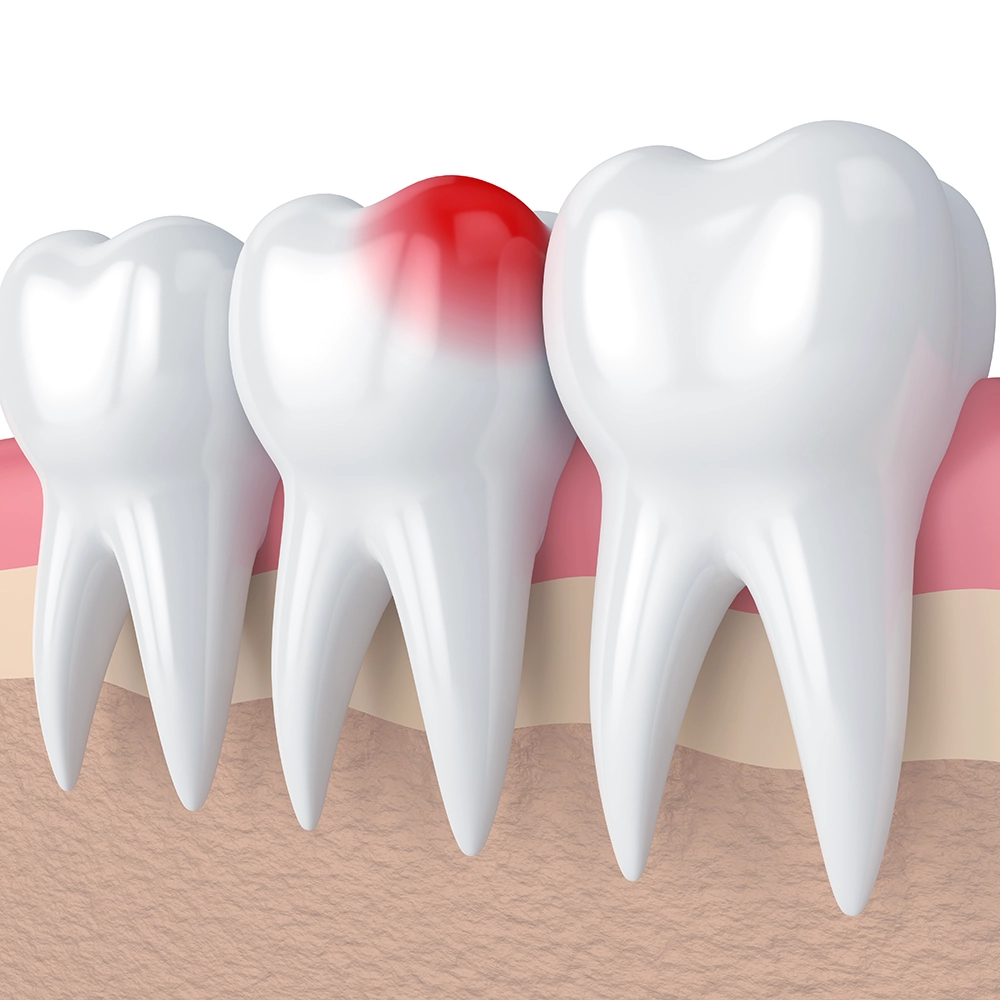

A 3D illustration of teeth in a gum line, with one tooth highlighted in red to indicate inflammation or infection, emphasizing the pain and urgency associated with dental emergencies.

Sudden Severe Toothache:

A sudden, severe toothache can be alarming and debilitating. This common dental emergency might be due to an abscess, a fractured tooth, or severe decay. Immediate attention is crucial to relieve pain and prevent further complications. Our team is here to provide prompt and effective care.